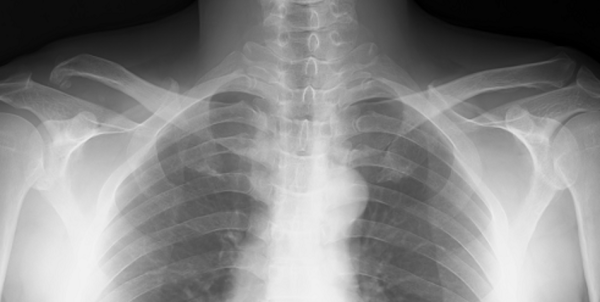

This X-ray was taken when he first came to my clinic in 2018. This shows dislocations of the right acromioclavicular. He also had pains on the shoulder when raising arms. In addition, he felt stiffness and discomfort on the neck, shoulder, and scapular.